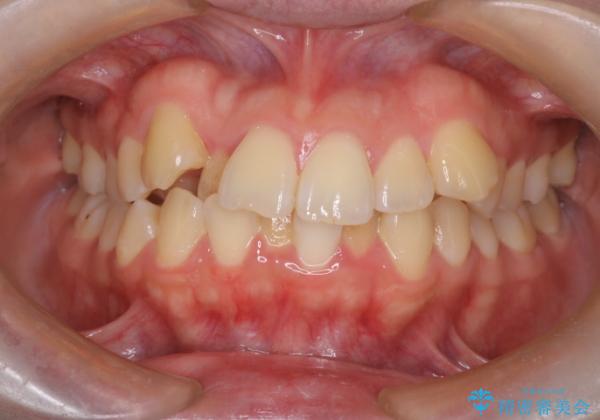

- 患者様は、結婚式までに歯並びを整えたいとのご要望で来院されました。診断の結果、上下左右の第一小臼歯を抜歯し、歯列全体を整える計画としました。審美性を重視し、目立ちにくいホワイトワイヤーを使用した矯正を提案しました。治療期間は2年を目安とし、結婚式までに前歯の整列と噛み合わせを優先的に整えるスケジュールで進めました。定期的な調整と経過観察を通じて、計画的に治療を進めました。

結婚式までに仕上げるため、通常よりも細かく調整を行い、歯の動きを効率的に管理しました。審美ワイヤーを使用したことで、治療中も目立ちにくく、写真撮影などの日常生活での見た目の負担を軽減しました。抜歯部分のスペースを閉じる際には、前歯の位置や噛み合わせのバランスに配慮し、過度な力がかからないよう進めました。患者様の大切なイベントに間に合うよう治療計画を立て、理想的な仕上がりを実現しました。